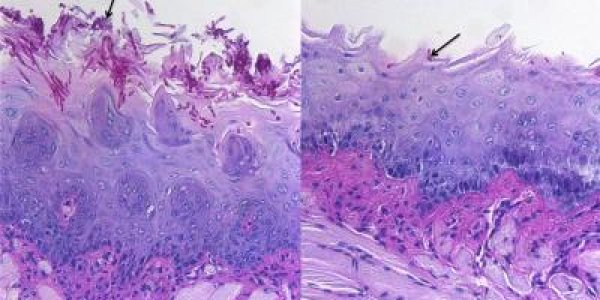

Are Eye-Safe Lasers Safe?

The modern world has a problem. We are undergoing spontaneous mutations caused by radiation, even at low levels. This radiation can break chromosomes into pieces that reattach randomly and sometimes…